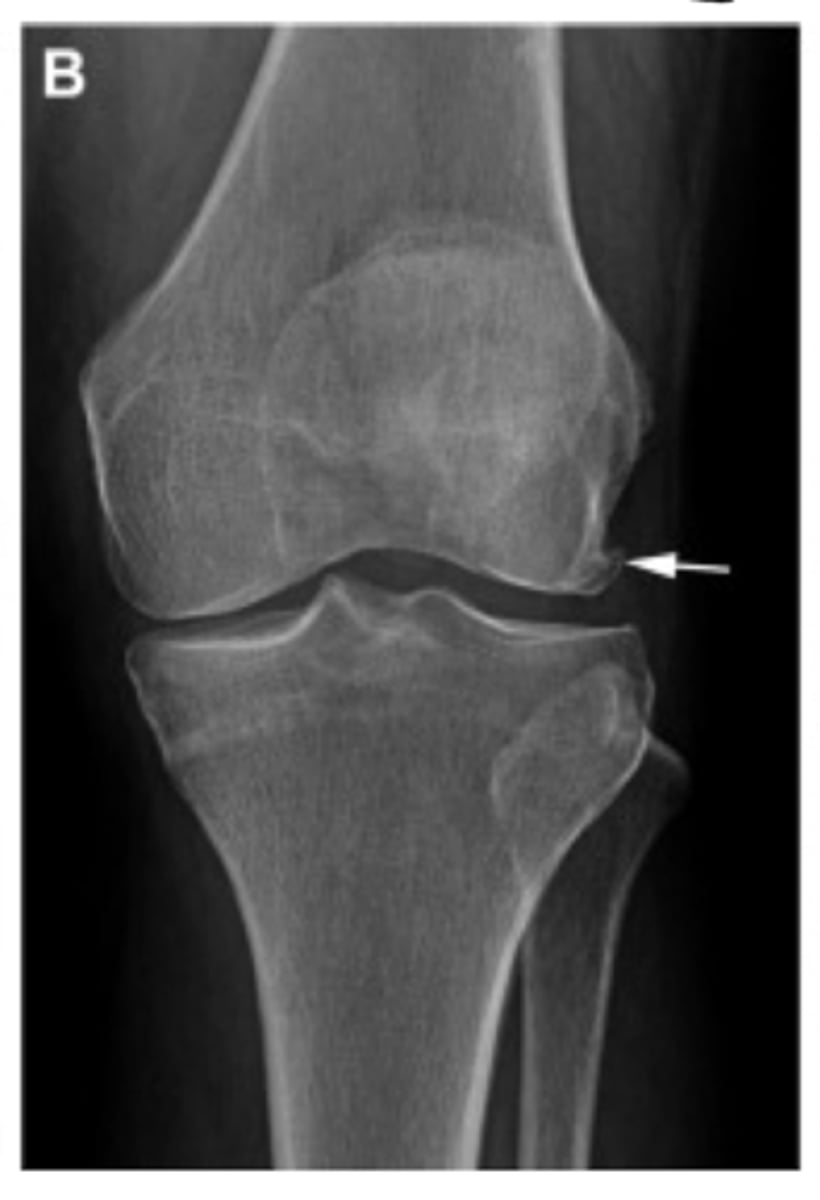

Grade I = minimal osteophytes w/ no problems w/ space or cartilage

Define the Kelgren Lawrence grade. How do you know?

Grade II = 1 definite osteophyte w/ NO space narrowing

Grade III = marginal osteophytes w/ space narrowing + sclerosis & multiple osteophytes

Grade IV = obliteration of joint space (bone on bone)